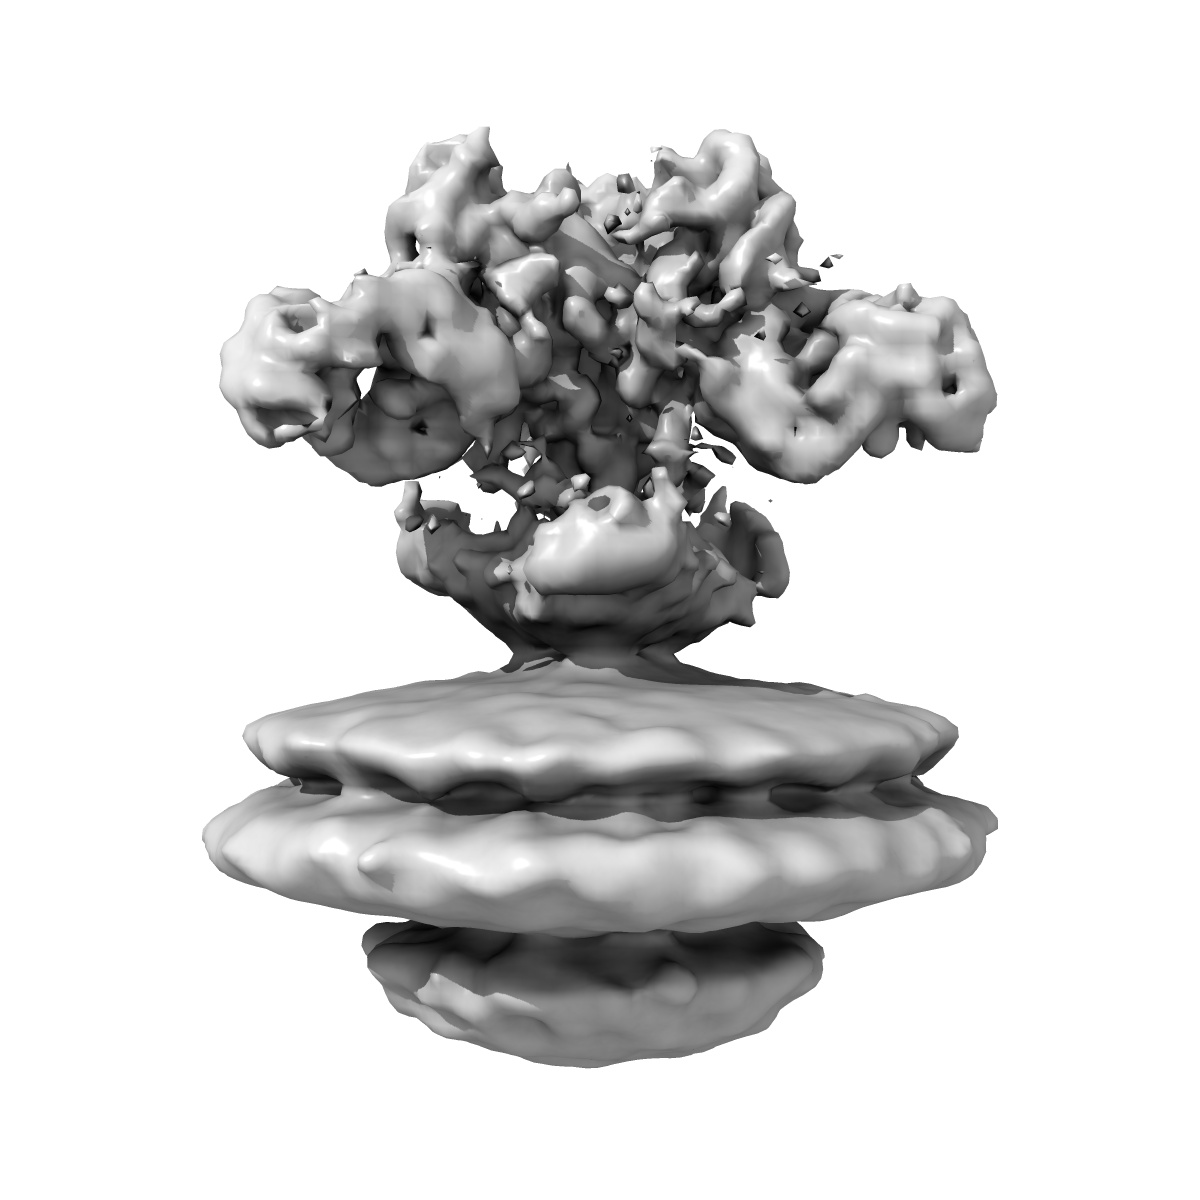

3A6 and KZ52 Fab fragments bound to Ebola GP, subtomogram average from a cylinder mask

Subtomogram averaging9.3 Å

Anti-Ebola virus mAb 3A6 protects highly viremic animals from fatal outcome via binding GP (1,2) in a position elevated from the virion membrane.